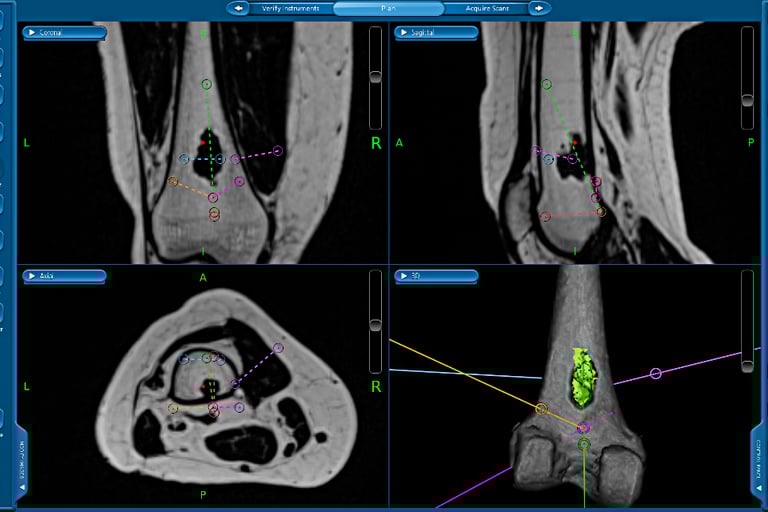

Management of these tumours can be very complex and Mr Pang is one of a few surgeons in Melbourne who has extensive experience in the surgical management of bone and soft tissue tumours / sarcomas. Management often include collaboration with other specialists of with similar interests (plastics, spinal and thoracic surgeons), complex resections such as the pelvis, utilisation of tumour / megaprosthesis and employing advanced computer navigation techniques to achieve precision tumour surgery.